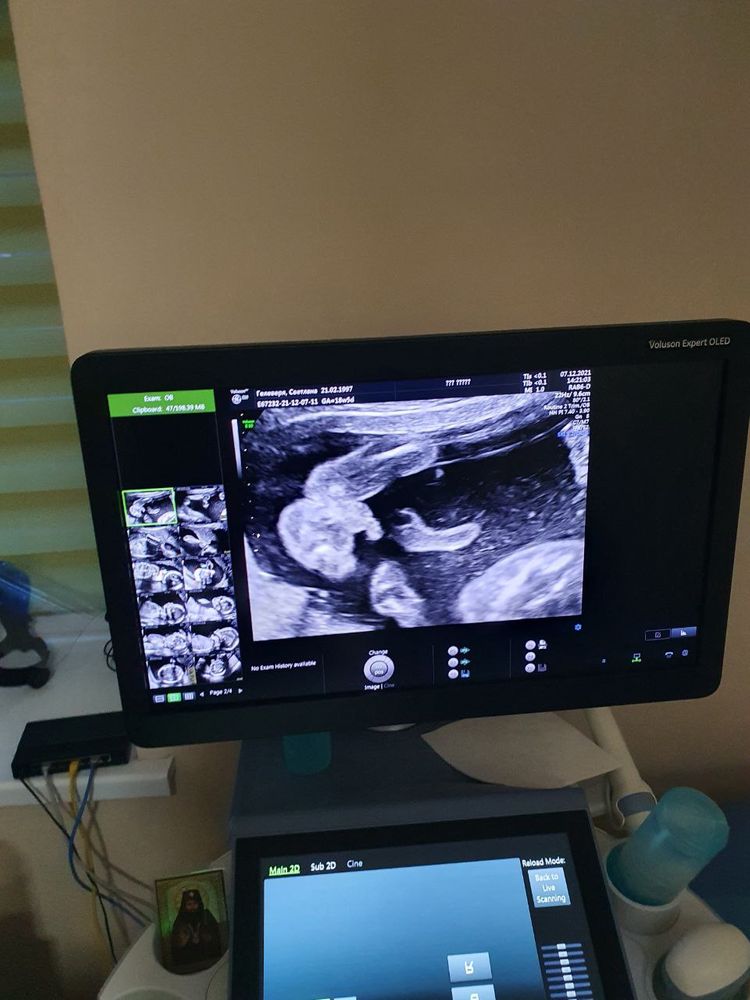

2й скрининг, 18+5 💙

Лилия, ух ты, поздравляю)) Меряли, забыла указать 😄 39мм абдоминально.)

Поздравляю с хорошим скринингом! Такое облегчение знать, что все хорошо) У моей в 19.5 вес 260 г был))

Марина, спасибо ❤ согласна, когда все хорошо это так хорошо) У меня муж крупный родился, я вот передиваю что сынок тоже будет не маленький 😄 врач особо ничего не сказал, но я посмотрела что да, такой веч на недельку больше должно быть. Ну будем следить)